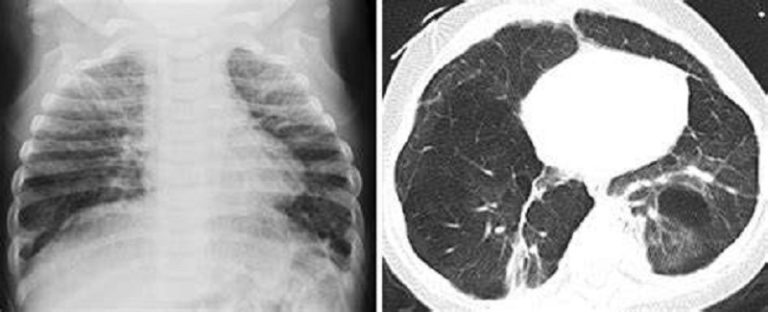

La displasia broncopulmonar (DBP) sigue siendo frecuente en recién nacidos prematuros; sin embargo, los criterios diagnósticos se basan en las necesidades de oxígeno a posteriori y en la radiografía.

La puntuación de la ecografía pulmonar semicuantitativa (ELP) ofrece una alternativa sin radiación a pie de cama. El objetivo de este estudio fue determinar la precisión diagnóstica dependiente del tiempo de las puntuaciones de la ELP para la DBP en neonatos prematuros.